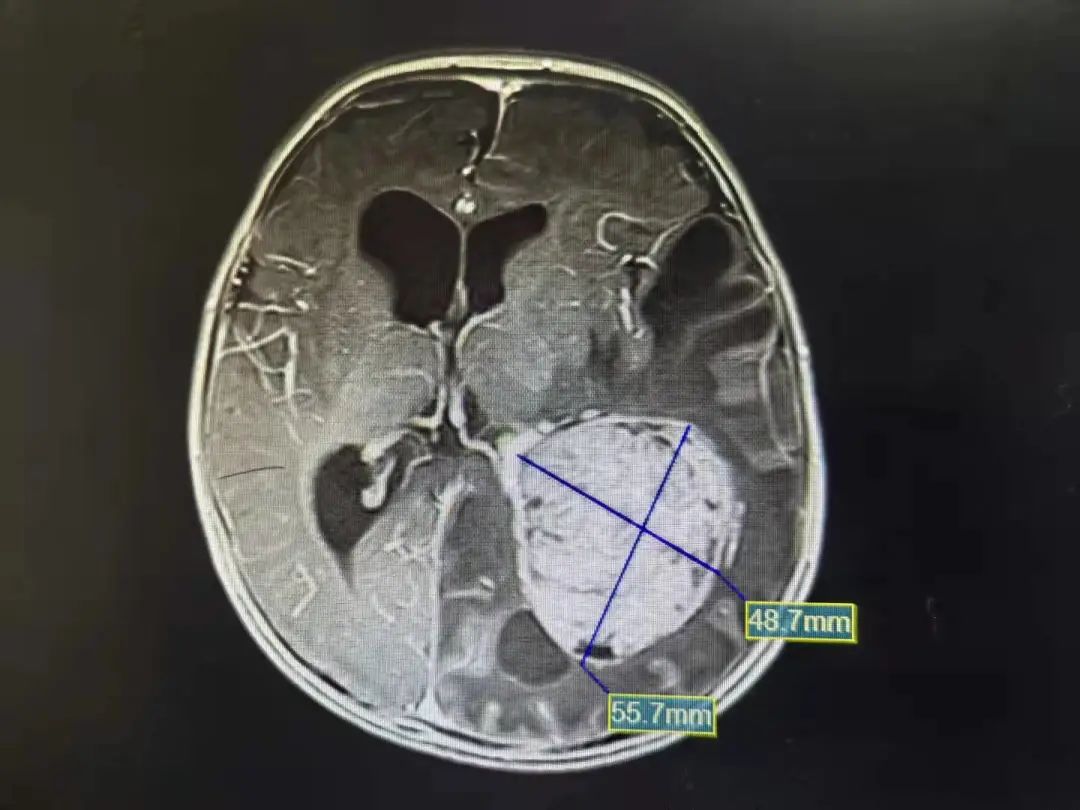

六六手术前脑部影像图

检查显示,六六虽然才三四个月大,头围已经达到了48CM,相当于两三岁的孩子的头围。颅内肿瘤的直径已超过5.5CM,就如同脑袋中被塞进了一个大鸭蛋。